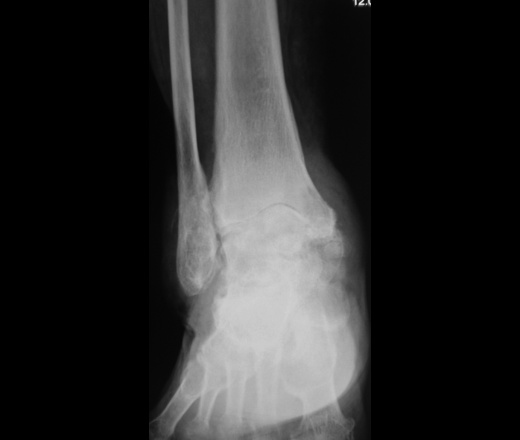

Фотографии рентгеновских снимков артрита голеностопа